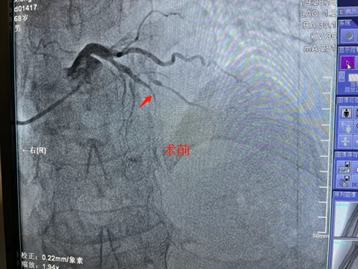

3月20日,是值得纪念的日子,商城县人民医院心血管内科心脏介入团队在郑州大学第一附属医院专家的指导下,顺利完成了6台高难心脏介入手术治疗,打破了我院开展PCI项目以来的单日最大量纪录,在我院心脏介入技术发展过程中具备里程碑式意义。 据心血管内科熊晨晖主任介绍,当日共有7人接受手术,其中6人分别完成了疑难复杂的支架植入和药物球囊治疗,术后血流再通良好,患者及家属对治疗效果均非常满意。 在北京安贞医院马长生教授团队的帮扶下建立的国家标准化心血管疾病中心,驻扎式派出叶益聪教授等专家的带教下及郑大一附院,郑大二附院知名专家的指导下,商城县人民医院心血管内科于稳中求进,不断探索学习,自2018年10月至今,已成功地完成支架植入治疗近600例,造福商城县广大心血管疾病患者。 一台台介入手术的圆满完成,一位位患者因及时救治而重获新生,无不体现着商城县人民医院心脏介入团队日益精进的诊疗技术,也显示出我院在介入治疗领域已具备较强的综合实力。时间就是生命,时间就是心肌,与时间赛跑,与死神搏斗!商城县人民医院心血管内科团队将会不懈努力,不断进取,为广大心血管疾病患者的健康保驾护航! 就医地址: 冠心病监护病房(CCU):2号病房楼4楼。 咨询电话:0376—7975373; 心血管内科病区:2号病房楼4楼。 咨询电话:0376—7973137